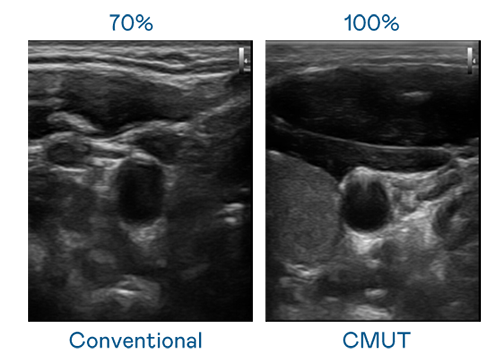

CMUT 技術是一種用電容式微機電元件來產生超音波訊號的技術。與傳統 PZT 壓電式技術相比,CMUT 頻寬增加 30%,更寬頻的超音波訊號讓影像解析度大幅提升,是實現高影像品質醫療超音波掃描、促進精準醫療發展的關鍵技術。

超音波影像的解析度高低,首先取決於探頭能發出的訊號頻寬。j9九游会(中国)官方网站 CMUT 可提供高清晰的超音波訊號,提供高頻寬、高靈敏度、影像紋理細節更高的超音波影像,協助醫護人員縮短影像判讀時間及利用精準的醫療影像進行診斷。